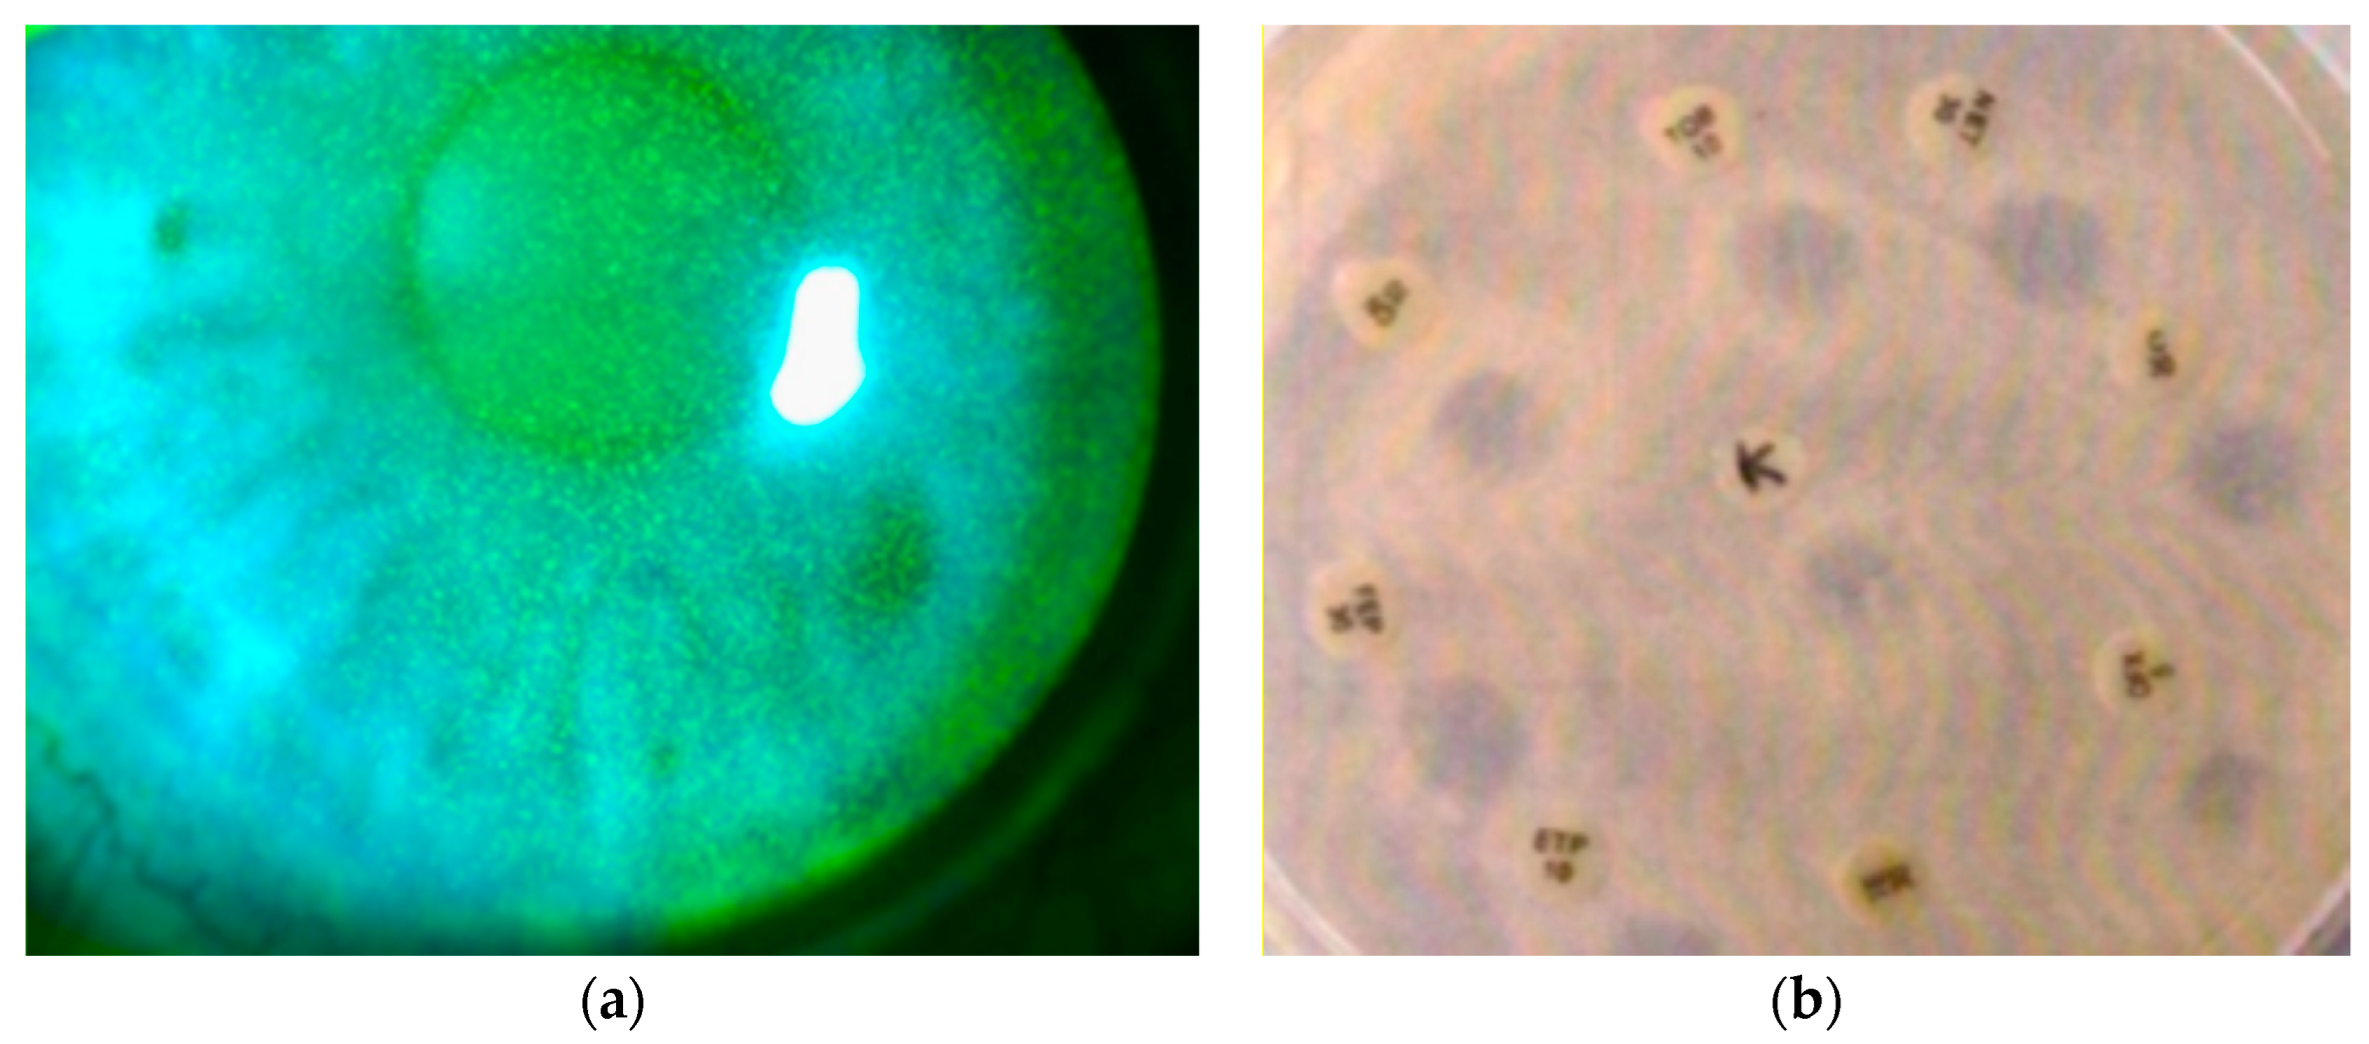

Efficacy and Safety of Keratosept Eye Drops in Patients with Punctate Keratitis: Clinical and Microbiological Evaluation on 50 Eyes

3. Results